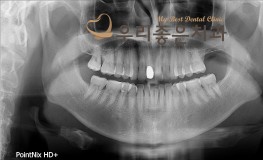

우리좋은치과 치아 상실로 인한 임플란트 보철 치료(김**2019.1.30~2019...

No.302

임플란트

2019-07-26

1418